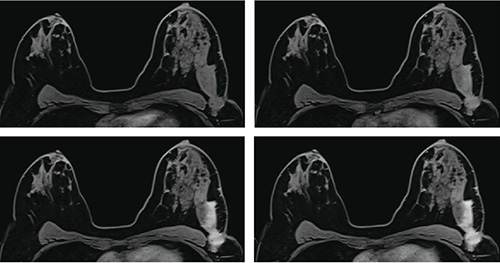

“TWIST-VIBE”を使用した造影ダイナミックスキャンにより,高い空間分解能を維持しながら,さらに高い時間分解能を持つ3D画像を得ることが可能となりました(図3)。TWIST-VIBEは,高速造影MRAで定評のあるTWIST法をVIBEシーケンスに組み込むことにより,従来以上の高速化が可能となりました。より早い時相からの造影強度曲線を得ることにより,診断のための新たな情報を得ることが可能となります。

図3 TWIST-VIBE ダイナミック画像

時間分解能5秒での3D画像